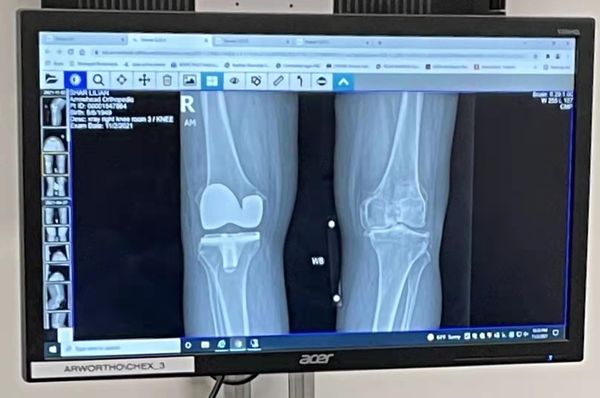

由于膝关节越来越疼痛,所以 夫君煜群和二弟志文陪同我到医院,还是请那位曾经给妈妈置换 过膝关节的印度医生帮我置换膝关节,医生要我先照膝关节X光,之后,医生告诉我,我的膝关节因各种原因发生磨损、软骨己被侵蚀掉了,还有骨刺,

半月板和膝关节韧带都损伤。 导致关节间隙狭窄,膝关节疾病通常会导致关节部位出现肿胀和疼痛,行走疼痛及功能障碍,并且伴随着活动限制,下蹲也非常困难。,严重影响生活质量。

左右膝关节的对比

主治医师查看我的膝关节X光片